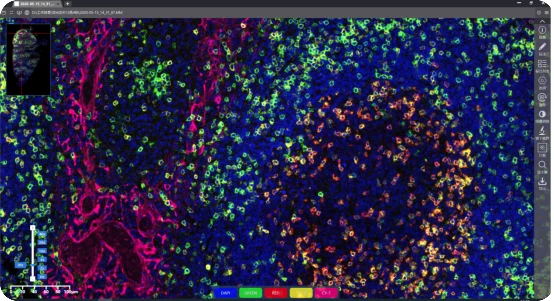

Fluorescence Scanning Features

KFBIO Digital Pathology Slide Scanners (fluorescence) have excellent performance in the accuracy of movement, focus, and image processing, and its accurate whole slide imaging not only meets the requirements of digital slide viewing and operation but is also suitable for AI-assisted image analysis.

Excellent Cross Color Suppression Design

Independent LED light source avoids cross color. High contrast, high brightness, no drift, and no cross color make it more suitable for specific fluorescence channels. Equipped with CHROMA filter narrowband filter, the minimum spectral band resolution reaches 10nm, which can efficiently separates different fluorescence channels to achieve large information density without affecting the quality of data.

Image Processing Algorithm

The fluorescence image stitching algorithm based on high-precision direct position feedback is used to splice images to obtain seamless whole-slide images and improve browsing experience. Pupil function of visual image enhancement algorithm is applied, no need to correct slides. The optical field information is efficiently estimated based on the limited excitation light information. When the light field information does not change with the increase of new sample, the light field information must be the right one for the set of optical path, and the light field can be calibrated based on this information.

Multiplex immunofluorescence scanning

FISH scanning analysis

Scientific research applications:

brain research, liver and stem cell research,

drug research and development

Tumor micro environment analysis/

spatial transcriptome analysis